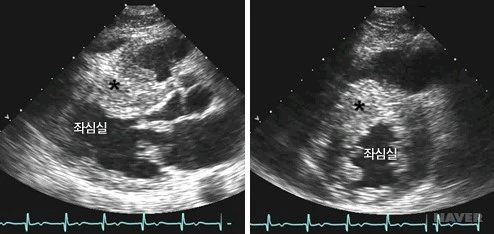

i1_AA000557_880.jpg?type=w530_fst_n&wm=Y

심실중격 비후성 심근증의 심초음파: 심실중격(*)이 좌심실 후벽에 비해 두꺼워져 있음